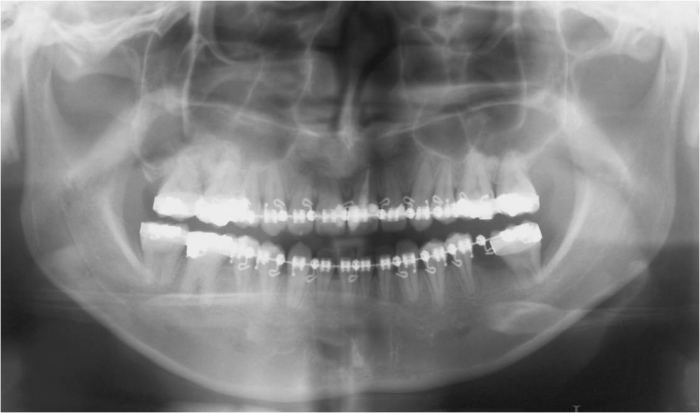

Raio x panorâmico inicial